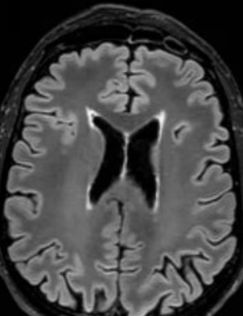

A radiologic diagnosis of Alexander disease is based on the presence of 4 out of 5 MRI features, which are most commonly observed in people with earlier age of onset (ie, infants and young children)1,15,16:

- Frontally predominant white matter changes1

- Periventricular rim abnormalities (eg, high T1-weighted signal and low T2-weighted signal)1

- Abnormalities of the basal ganglia and thalami1

Unlike multiple sclerosis, Alexander disease is not associated with generalized brain atrophy23; it may also be distinguished by the presence of symmetrical lesions on MRI.54 A spectrum of atypical MRI findings, including ventricular garlands, swelling of the medulla, tumor-like presentations, and inflammatory features, have also been documented.55-61

An additional imaging pattern characterized by bilateral symmetric hyperintensity on T2-weighted imaging involving the central inferior olivary nucleus, the pyramids, and the cuneate and gracile fascicles, with sparing of the peripheral inferior olivary nucleus and inferior peduncle (termed the “chipmunk sign”), is a common feature in people with Alexander disease regardless of age of onset.62